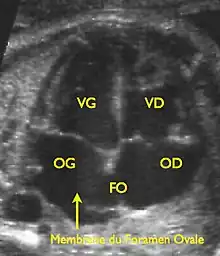

Le foramen ovale est un passage « en chicane » entre les deux constituants principaux de la cloison inter-auriculaire, le septum primum et le septum secundum, faisant communiquer les deux atriums. Il tend à être fermé par une membrane (« la membrane du foramen ovale ») qui n'est maintenue en position ouverte que par la différence de pression régnant dans les atriums.